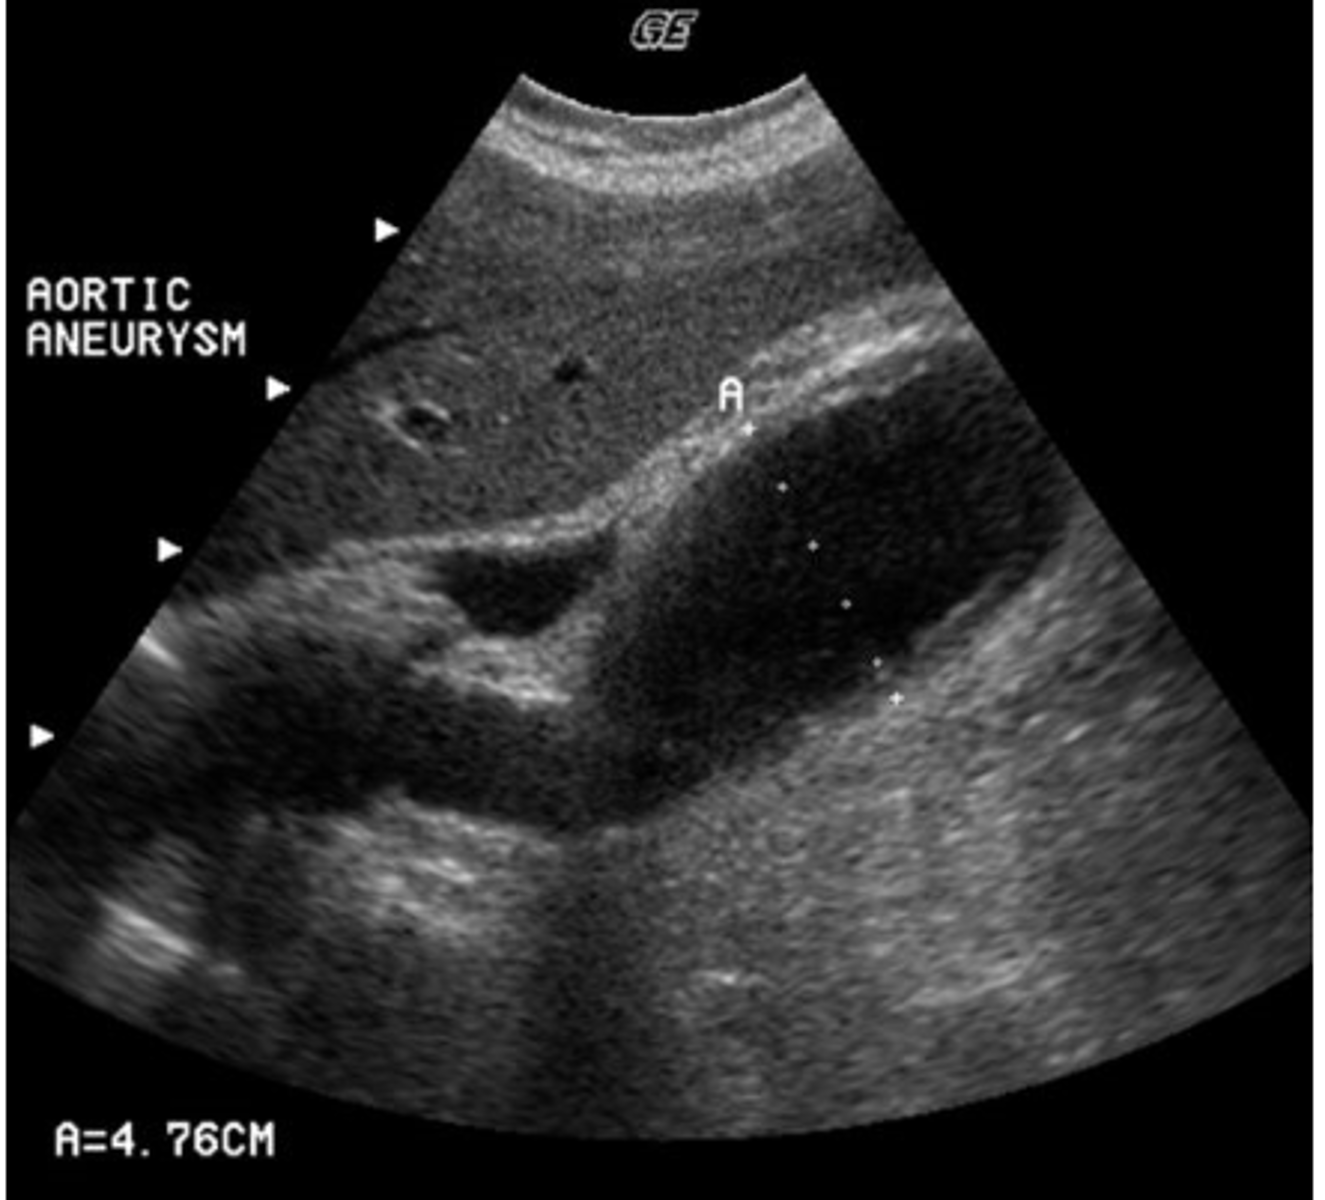

d. fusiform

You are asked to perform a follow-up study on a patient with a known abdominal aortic aneurysm. Which of the following terms correctly describes this aneurysm?

a. pseudoaneurysm

b. saccular

c. dissecting

e. dumbbell

b. b

Which of the following shows the correct plane for measuring the diameter of this aortic aneurysm?

a. a

c. c

d. d

e. both b and c are correct